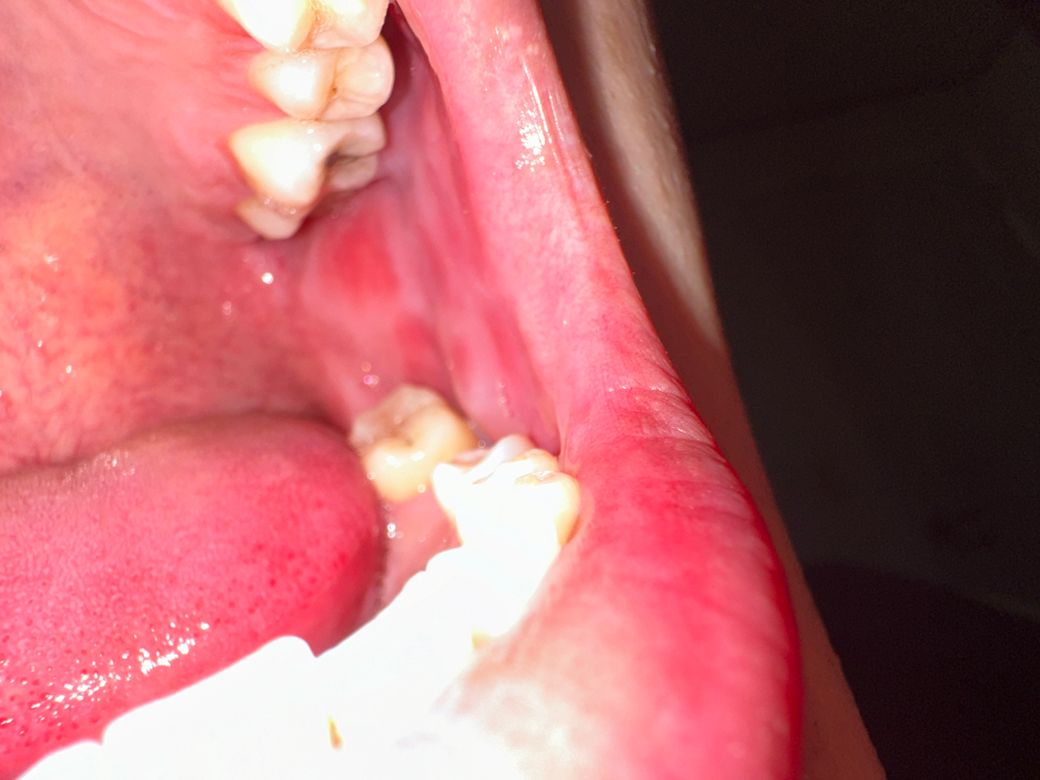

사랑니 발치 후 볼 하얀색같은게 생겼어요

사랑니 발치 후 6일차 입니다. 맥주 두캔정도 먹었는데 볼이 부어서 확인해보니 볼에 하얗게 올라왔습니다.

아픈곳은 없는데 혹시 뭐 때문인가요..

• 1번 째 사진

사진으로는 큰 문제가 보이진 않습니다 음식을 먹을 때 너무 강한 힘이 작용하게 되면 볼 속에 있는 연조직을 치아쪽으로 밀어내면서 하얀색 조직이 생길 수 있습니다 음식을 천천히 먹거나 너무 강한 힘으로 먹지 않는 것이 좋습니다

저부분은 볼살이 치아에 씹혀서 생긴 자국입니다. 큰 문제가 잇는건 아니니 너무 걱정하지 않으셔도 됩니다.

해당부위에 구내염이 발생한 것으로 보이며, 염증이 덧나지 않도록 음주는 피하고, 소독용 가글액인 헥사메딘가글액으로 가글하여 관리하는 것이 증상경감에 도움이 됩니다.